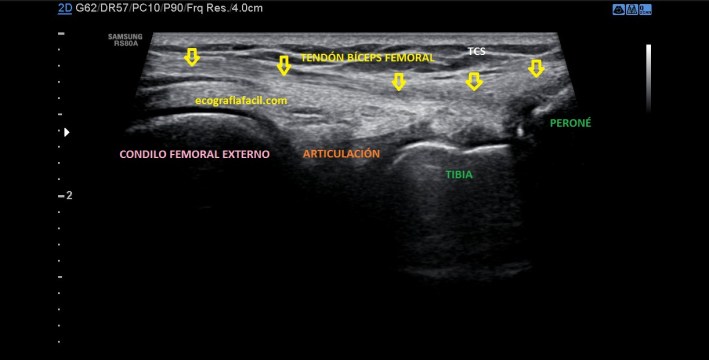

La inserción del Bíceps Femoral es diferente, lo hace, tanto su porción larga, como su porción corta, unidas, en la cabeza del Peroné, por tanto lateral. Mira:

Normalidad

Esta es una imagen, conseguida con un corte longitudinal, en situación normal…mira la misma imagen en una situación de rotura del Tendón del Bíceps Femoral:

Patología

En la imagen patológica que ves arriba es vital la localización del Peroné. Ahora te voy a pedir que compares y que observes como en la imagen de normalidad vemos un tendón hiperecogénico, marcado por flechas amarillas, homogéneo insertando en el Peroné…en la imagen siguiente el tendón está aumentado de tamaño, heterogéneo y con componente líquido, lo marcan las líneas rojas…Es precioso, ¿verdad?…ambas imágenes son de deportistas, una corredora y amiga, la imagen de normalidad y un futbolista, la imagen patológica.